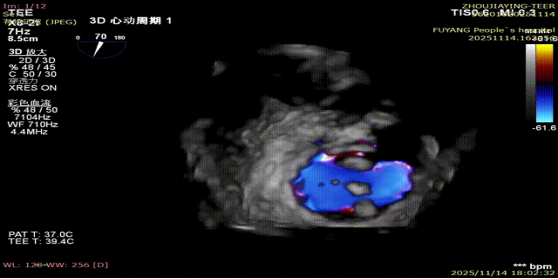

手术当日,在全身麻醉及TEE全程导航下,陈玺全副主任团队凭借丰富的临床经验与精湛操作技巧,顺利完成房间隔穿刺、瓣叶精准定位等关键步骤。针对患者二尖瓣A2/P2 区域反流靶点,团队精准夹合瓣叶,经X-plane技术与三维超声反复确认夹持质量后,成功释放一枚MitraClip XTR夹子。术后即时评估显示,患者二尖瓣反流由术前3 +重度降至轻度,平均跨瓣压仅3mmHg,手术达到预期效果,全程无并发症发生。

术前MR反流

术后第二天,患者顺利返回普通病房,并可自主下床活动,进食、睡眠等生活状态逐步恢复正常。术后超声显示残余轻度反流,肺静脉血流恢复正常,患者症状较前明显改善,活动耐量提升,生活质量显著提高。术后1周,患者各项生命体征平稳,顺利康复出院。“没想到不用开胸就解决了这个大毛病,还能恢复这么快、这么好!”出院当天,患者及家属对手术效果和就医体验给予高度评价,并衷心感谢医护人员的专业诊疗和无微不至的关怀照护。